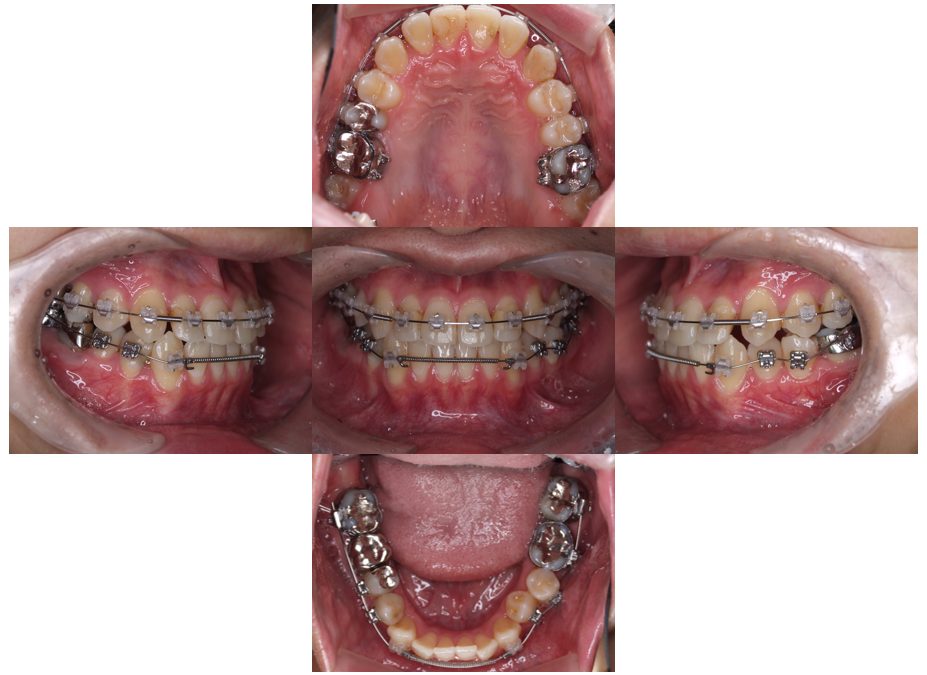

矯正治療・インプラント治療・セラミック治療の症例紹介(三隅歯科クリニック)

三隅 賢祐(三隅歯科クリニック)

症例詳細

| 主訴 | 30代女性 顎関節が痛い。見た目も気になる |

| 治療内容 | 矯正治療を行いました。 |

| 治療費 | 1,700,000円(税込み) |

| 治療期間 | 3年(矯正治療期間 2年半) |

| 治療回数 | 40回 |

| 想定されたリスク | 術前に精密な診査診断とシミュレーションを行い、インプラントを適正なポジションに埋入しておかないと、インプラント自体が矯正治療の邪魔になるリスクがあった。 |